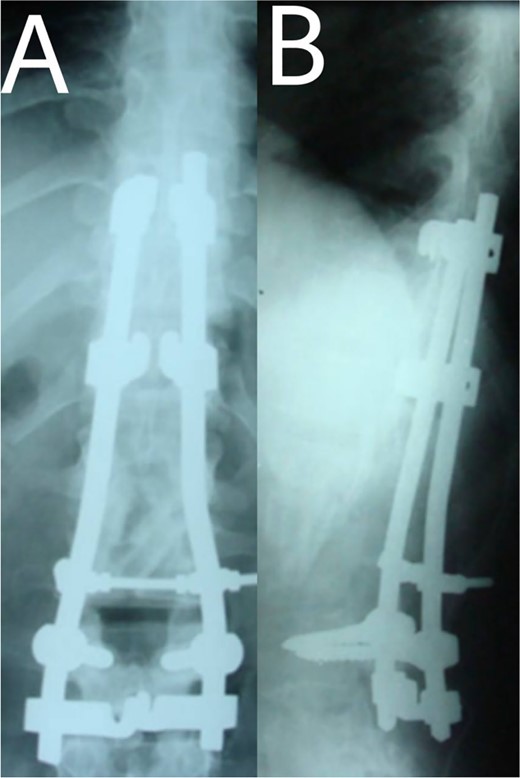

A 24-year-old farmer female was admitted to the Department of Neurosurgery with low back pain, no fever, cough, motor deficit, or any symptoms. Medical, surgical, family histories and physical examinations were unremarkable. The laboratory findings showed a white cell count of 9.8 × 103/μL, C-reactive protein concentrations of 20, erythrocyte sedimentation rate of 50 mm/1 h, 90 mm/2 h and tuberculin skin test was positive. X-ray films showed the collapse of the L1, L2 vertebrae, and L1–2 intervertebral space (Fig. 1). An abscess was observed at the L1–L2 vertebral level in lumbar magnetic resonance imaging (MRI) (Fig. 2). Chest X-rays and Sputum smear were negative. The patient was treated with anti-TB treatment (Isoniazid, Rifampicin, Ethambutol, Pyrazinamide) due to spinal TB findings on MRI (Fig. 3). After 40 days, the patient was diagnosed with grade 1/5 lower limb weakness, and bladder and bowel dysfunction, with no impairment in sensation, which predicts spinal infection. MRI confirmed these abnormalities and showed typical findings such as vertebral endplate destruction, bone marrow and disk signal abnormalities, and paravertebral or epidural abscesses (Fig. 3). Due to clinical manifestations and MRI spinal TB findings (Fig. 3), the patient underwent surgical debridement, interbody fusion and internal fixation with fibular autografting and supplemental posterior spinal stabilisation using a posterior-only approach. On post-operative follow-up, the treatment continued for 9 months, in addition to physical therapy for lower limb weakness. In the end, the patient returned to full motion with grade 5/5 in the lower limb, normal sensation, and no bladder or bowel incontinence. No recurrence was observed in the grafting area. Radiologically 2, 6 and 12 months, 14 years’ post-operation, the patient had achieved full bony graft spinal fusion (Figs 4–6).

(A, B) Complete bony incorporation between the implanted fibular autograft and host vertebral body was noted on the lateral radiograph 1, and 14 years later.

Even though a spinal epidural abscess is a rare infectious situation, its incidence is increasing due to risk factors such as chronic illnesses, immunodeficiency states and drug abuse. MRI is an effective diagnostic test for spinal infection and to differentiate between TB and pyogenic spondylitis. It is difficult to determine the diagnosis when there are atypical manifestations of infectious spondylitis. However, in our case, MRI demonstrated the typical finding such as the compression of the spinal cord by the two vertebral endplates destruction, the epidural abscess, the disk signal and bone marrow abnormalities. Conservative therapy is the basis of spinal TB treatment. This approach is insufficient in some cases that require surgical interventions [4]. When indicated, delayed surgical management may lead to a bad prognosis [5]. As in our case, the paraparesis developed after 40 days of TB drug administration. These aspects necessitated surgical procedures to prevent further spinal cord compression [6]. Surgical techniques included posterior approach decompression, abscess resection, bone grafting and instrumentations. Spinal TB primarily impacts the anterior elements due to its blood supply profusion. Hence, the conventional approach has long been to use the anterior approach in spinal TB treatment [6, 7]. A prospective study has shown that the anterior approach has good results in a minimum period of a 3-year follow-up. Also, Ge et al [8]. reported a case of spinal TB involving the L1 vertebra with a massive paravertebral abscess. They used the anterior approach in the decompression and grafting with posterior instrumentations and their results were satisfactory. However, in recent years, the posterior approach proved its advantages, including its familiarity, enough space for an adequate debridement of the focal lesion, in addition to less surgical invasion. Both approaches lead to reduced operation duration and fewer rates of complications [9]. On the other hand, the anterior approach has its risks, such as abdominal visceral injury, and neural and vascular injuries. Moreover, spinal instability may occur [10]. As for grafting, we used an autogenous bone graft from the fibula for osseous loss, which may be considered a golden standard, because of its immune correspondence and osteoinductive capability [4]. There are considerations about inserting a bone graft in an infected site, like the surrounding tissue’s capability to provide the biological background for recovery. The presence of biomechanical stability enables biological reactions to enhance bone ingrowth [11]. Bansal et al. reported the fibular strut graft efficacy along with cancellous graft in an anterior approach and without instrumentations [12]. Singh et al. also showed the same results but without cancellous graft [7]. In our case, the bone graft was supported with the posterior (T10–L3) hooks combination and screws. Spinal cord decompression is the priority. Besides, the infected extracted tissues had to be replaced with another component for the spinal column stability. The X-ray showed a successful fusion post-operation. The medication was administered for 9 months to prevent the recurrence of the infection [13]. After treatment, the muscle strength became 5/5 up from the pre-operative 1/5. Within 14 years of follow-up, the X-ray demonstrated a good bone fusion and the patient’s status was good (Fig. 6). Minimally invasive spinal surgery (MISS) has been used increasingly over the past two decades [14]. MISS is performed using smaller incisions instead of traditional open approaches to accomplish spine surgical operations. MISS includes spinal endoscopy and robotics, which has improved the accuracy of instrumentation placement and virtual/augmented reality that has been very helpful for practicing surgical skills without patients. These techniques decreased the sedation requirements, blood loss and hospitalisation time [15]. In conclusion, early diagnosis of TB spondylitis with proper treatment and surgical intervention immediately after a neurological deficit can protect the patients from the chronic spinal deformity. The posterior approach was sufficient and effective in our case. However, the surgical procedure should be planned on a case-by-case basis. Fibular graft and instrumentations were effective, although they were inserted on an infected background.